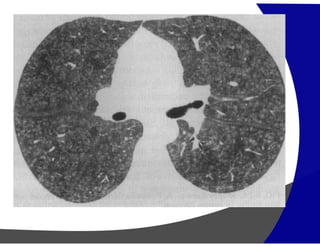

Opacidades em Vidro Fosco

(Pneumonia Descamativa Intersticial)

(Pneumonia por Pneumocystis carinii)